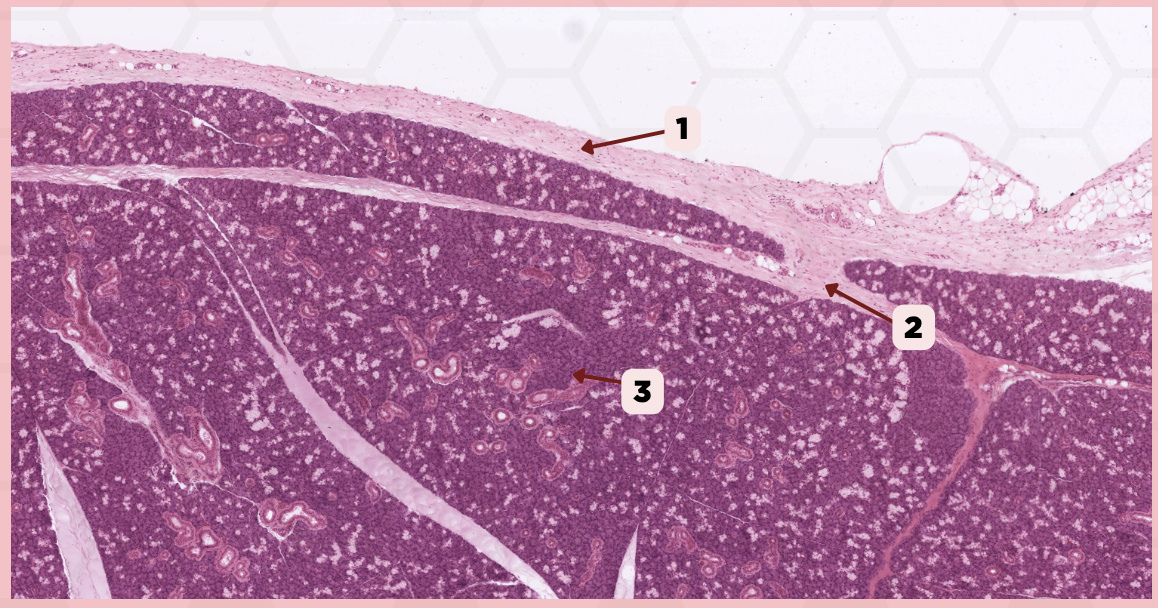

Submandibular

Identify the specimen.

Capsule

Identify the structure labeled as 1.

Septa

Identify the structure labeled as 2.